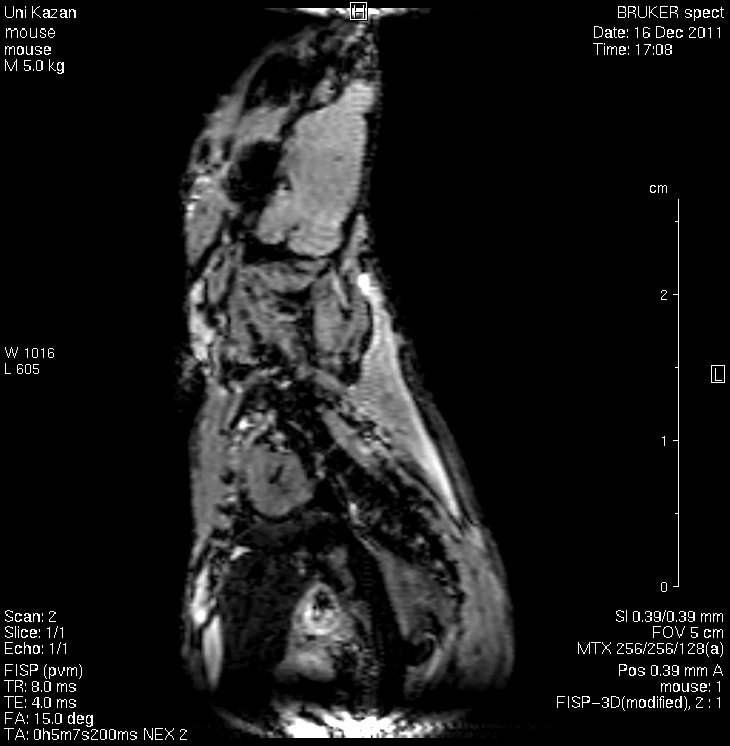

The Department of Physics of Molecular Systems is a team of professionals specializing in studies of the structure and dynamics of complex molecular and biomolecular systems using nuclear magnetic resonance (NMR) methods. It uses the most advanced nuclear magnetic resonance techniques, including gradient NMR and magnetic resonance imaging, as well as theoretical studies using modern numerical methods and computer modeling.